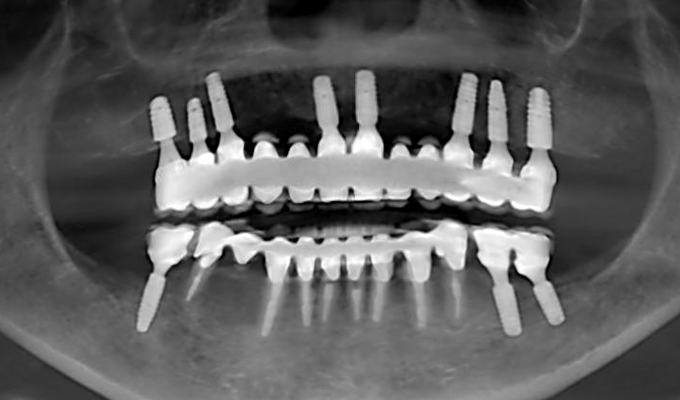

case1インプラントとメタルボンドブリッジの症例

初診時(2010年)

- 初診時の年齢

- 60代女性(2010年)

- 主訴

- ちゃんと咬めるようになりたい。最近孫が生まれたから一緒に歌ったりしたいけど、今は歌うこともできないから・・・・。と

- 治療内容

- 5年ほど前に入れ歯を作ったそうですが合わなかったので使用してなかったせいか前歯がグラグラになっていて今にも抜けそうな状態でした。

保存が難しい歯を抜歯し、上はインプラント8本、下は奥歯にインプラント4本埋入しました。

補綴は変色しないメタルボンドを選択されたので治療完了して11年経過してもとてもきれいな状態で維持されています。

初診時にお話しされていたお孫さんも中学2年生になったそうで、歯の治療をしたおかげで充実した毎日が送れてます、とメンテナンス時もいつも嬉しそうにされています。